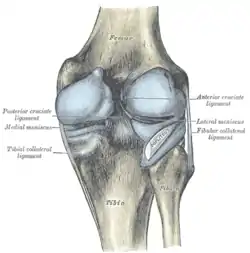

Cruciate ligaments

Cruciate ligaments Left knee-joint from behind, showing interior ligaments.

Intracapsular

The knee is stabilized by a pair of cruciate ligaments. These ligaments are both extrasynovial, intracapsular ligaments.[17] The anterior cruciate ligament (ACL) stretches from the lateral condyle of femur to the anterior intercondylar area.[13] The ACL is critically important because it prevents the tibia from being pushed too far anterior relative to the femur.[13] It is often torn during twisting or bending of the knee.[18] The posterior cruciate ligament (PCL) stretches from medial condyle of femur to the posterior intercondylar area. This ligament prevents posterior displacement of the tibia relative to the femur.[13] Injury to this ligament is uncommon but can occur as a direct result of forced trauma to the ligament.

The transverse ligament stretches from the lateral meniscus to the medial meniscus. It passes in front of the menisci. It is divided into several strips in 10% of cases.[10]: 208 The two menisci are attached to each other anteriorly by the ligament.[19] The posterior (of Wrisberg) and anterior meniscofemoral ligaments (of Humphrey) stretch from the posterior horn of the lateral meniscus to the medial femoral condyle. They pass anterior and posterior to the posterior cruciate ligament respectively.[13][10]: 208 The meniscotibial ligaments (or "coronary") stretches from inferior edges of the menisci to the periphery of the tibial plateaus.